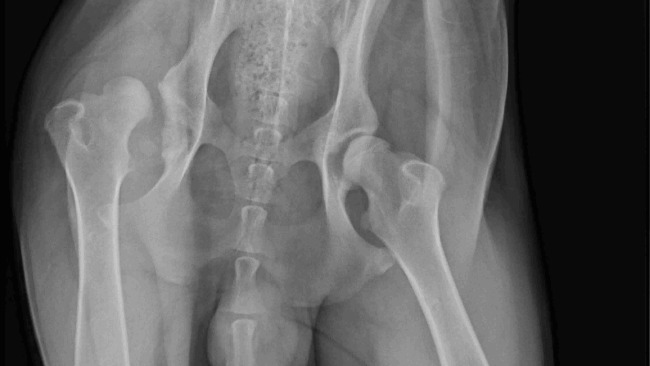

Cześć, nazywam się Berry, mam dopiero 10 miesięcy, jestem już 45 kg Bernardynem, lubię długie spacery, lubię dużo biegać i bawić się z moim rodzeństwem, niestety od dłuższego czasu bardzo cierpię, ponieważ stwierdzono u mnie ciężka wrodzona dysplazje lewego stawu biodrowego. To co lubię najbardziej sprawia mi ból, nie mogę dużo biegać i chodzić. Nigdy już nie będę normalnie chodził, jedyne co mogę to nie czuć bólu i móc normalnie funkcjować, jednak do tego jest potrzebna operacja, niestety jest ona bardzo kosztowna.